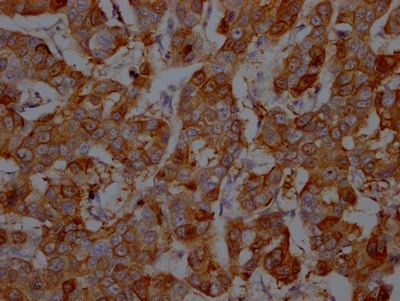

IHC image of CSB-RA958800A0HU diluted at 1:100 and staining in paraffin-embedded human breast cancer performed on a Leica BondTM system. After dewaxing and hydration, antigen retrieval was mediated by high pressure in a citrate buffer (pH 6.0). Section was blocked with 10% normal goat serum 30min at RT. Then primary antibody (1% BSA) was incubated at 4℃ overnight. The primary is detected by a Goat anti-rabbit IgG polymer labeled by HRP and visualized using 0.05% DAB.